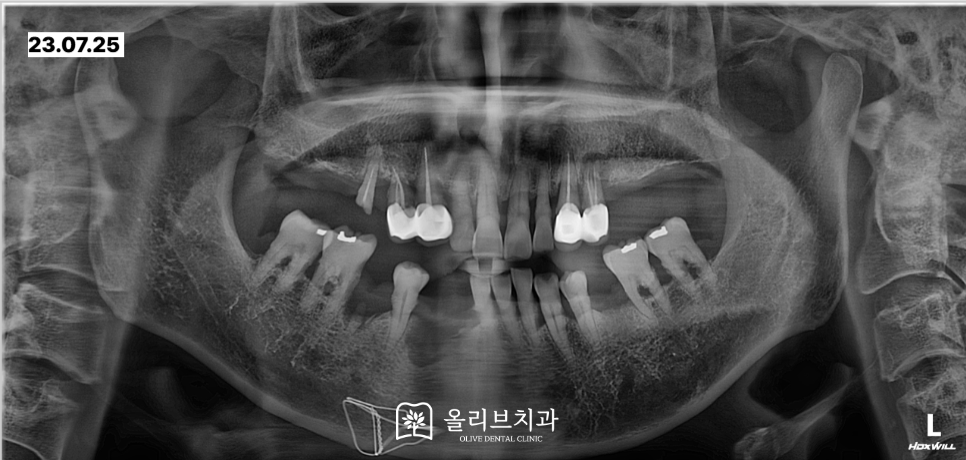

전체적인 상태를 체크하기 위해서 촬영한 파노라마 x-ray입니다. 위쪽의 큰 어금니들은 내원하셨을 때 이미 상실된 상태였습니다.

상악 우측 작은어금니는 뿌리만 남아있으며 상악 좌측 작은 어금니에는 뿌리 끝 염증이 발생해 있었습니다.

x-ray상에서 보면 하악의 치아가 위치한 치주부분들이 좋지 않아 잇몸뼈가 많이 내려간 상태여서 치아가 전반적으로 흔들리는 상황이었습니다.